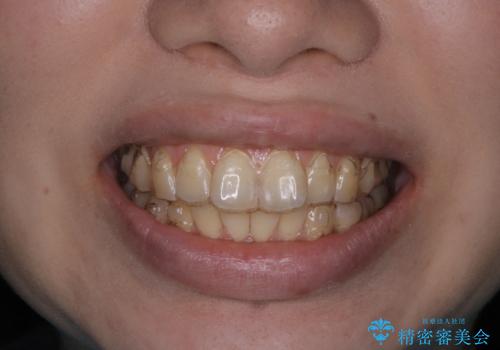

インビザラインでの治療中の患者様のクリーニング前後写真です。

- インビザライン矯正中に茶色が気になるとのことで来院されました。PMTC30分コースを行いました。

矯正治療中は虫歯や歯周病リスクが高くなります。

ぜひ定期的なクリーニングをおすすめします。